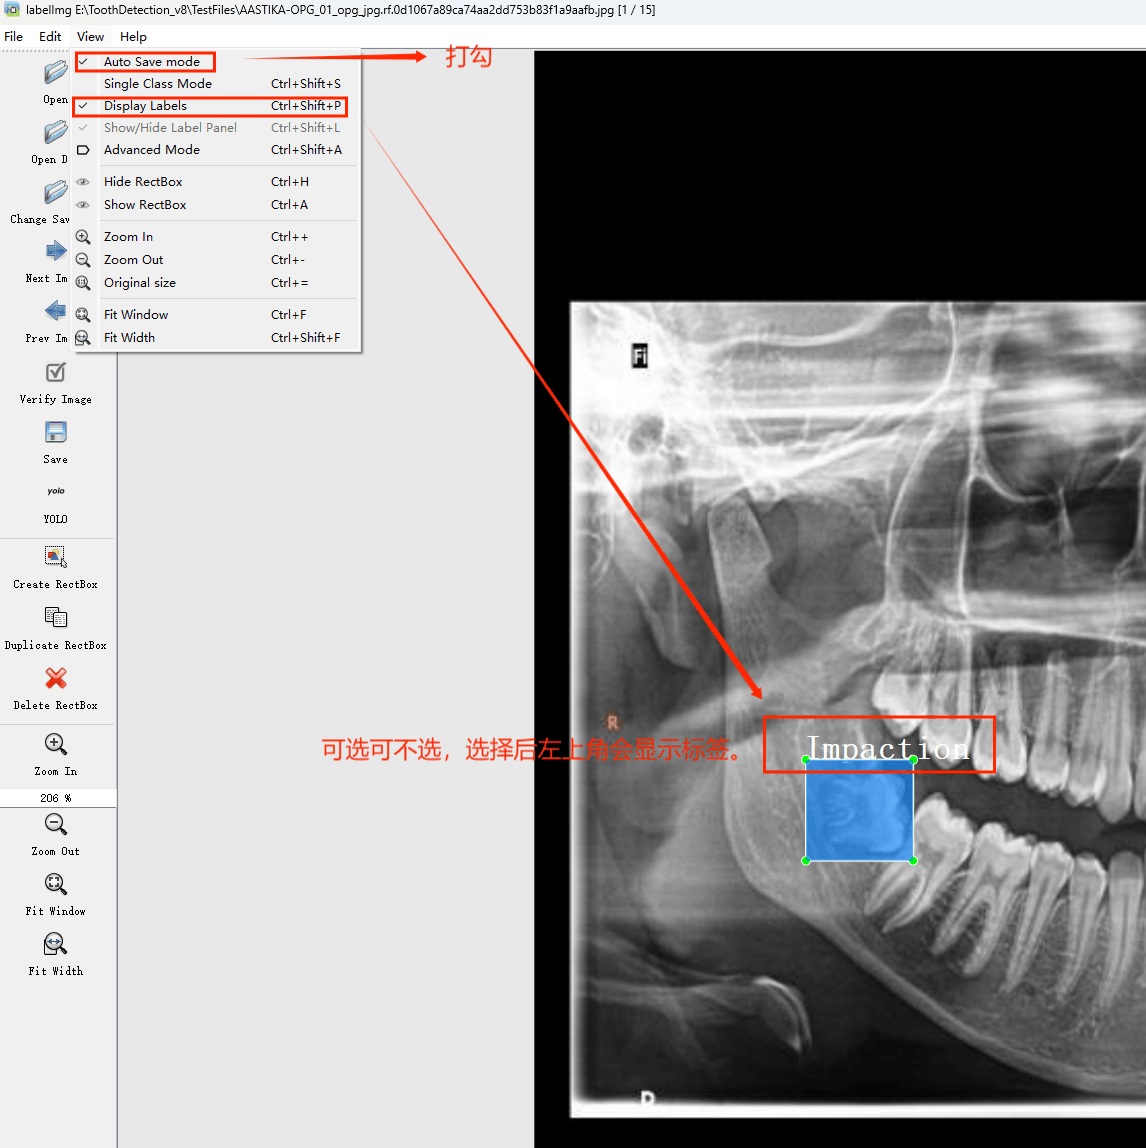

通过搜集关于数据集为各种各样的口腔牙齿CT影像相关图像,并使用Labelimg标注工具对每张图片进行标注,分6检测类别,分别是’阻生牙’,’龋齿’,’根管治疗’,’修复体’,’牙体修复’,’残根’。

初识labelimg

打开后,我们自己设置一下

在View中勾选Auto Save mode

接下来我们打开需要标注的图片文件夹

并设置标注文件保存的目录(上图中的Change Save Dir)

接下来就开始标注,画框,标记目标的label,然后d切换到下一张继续标注,不断重复重复。